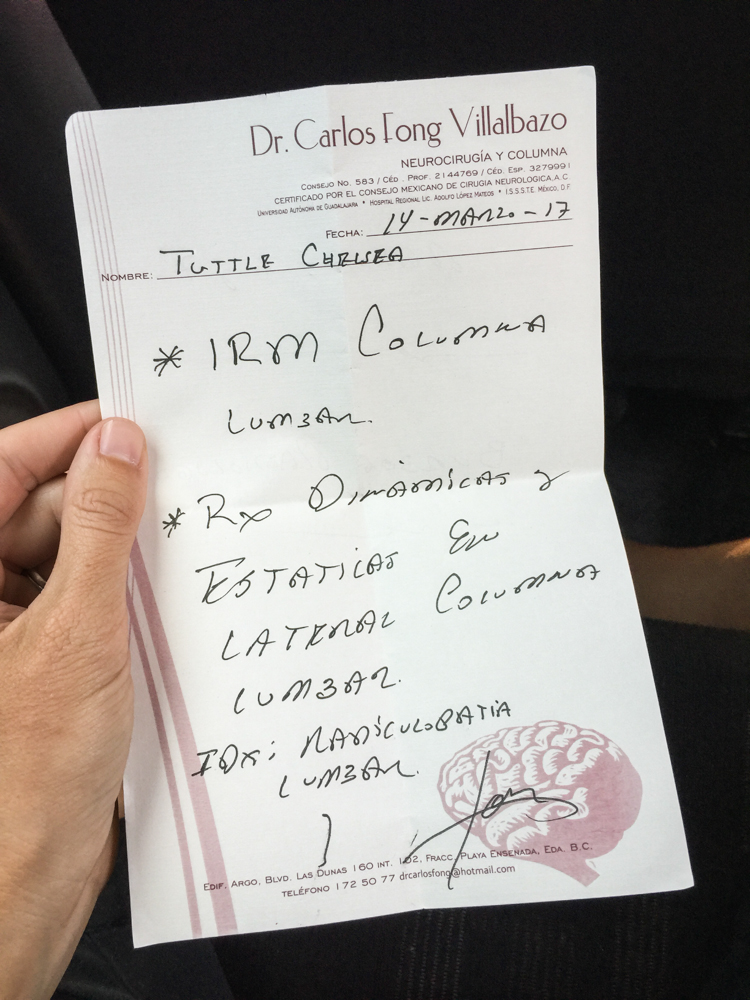

I have my first appointment with Dr. Fong. He gives me a small examination and tests my movement after having me describe my symptoms. Appointment ends with him writing me a referral for an MRI and some X-rays. I ask if I need to set up an appointment to get them, he says, "No, just show up in the morning and they'll set something up."

Total cost for appt: $35 USD

Another appointment with Dr. Fong for a follow-up to have him read the films and diagnose. Burboa had sent him the scans online, so he'd been able to review them before our meeting. His first comment when I walk in the door is, "I don't know how you're still walking!" He identified two herniated discs…one between L4/L5 and another, the culprit behind my pain, between L5/S1. He recommends surgery (a microdisectomy with nucleotomy in L5/S1). We decide to think on it, and he gives me his cell phone number to call or text him when we've made a decision. He also says I will have to get labs and blood work done beforehand, but that can be done without an appointment at his clinic.

Total cost for appt: $35 USD